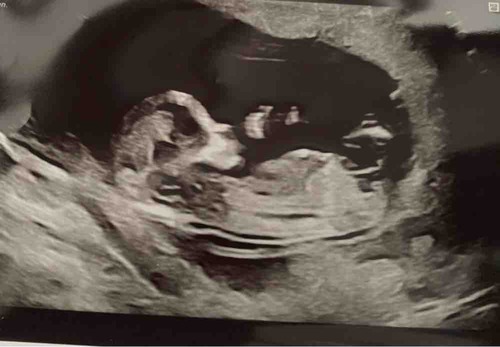

Blauw: omranding

Rood: Blaas

Groen: stand nub en blaas met ruggengraad

Zoals je kan zien in de ingezoomde echos met alleen blauw zie je een klein bolletje/boven de nub lijn. Dit is normaal het begin van de ontwikkeling van de pipi

De lijn van de nub veranderd dan in de balletjes.

Zoals op de echo met de andere kleuren lijnen is er meer schaduw bij gedaan waardoor je ook duidelijker ziet dat de nub omhoog staat. De blaas zit ook erg laag en van nub naar blaas naar ruggengraad staat het in een hoek naar de ruggengraad(📐) dit duidt op een jongen. Bij meisjes loopt het gelijk of bijna gelijk aan de ruggengraad(=) de blaas zit daar dichter tegen de nub aan en is de nub plat en is er geen bolletje.

Dus ik gok jongen

Erg lastig. Vaak verwacht ik wat meer te zien maar lijkt of met de 13 weken echo ze expres de nub wat minder goed op beeld zetten. Op het moment gok ik toch jongen. Door het bolletje erboven en de blaas die lager ligt. Je had niet nog een echo?